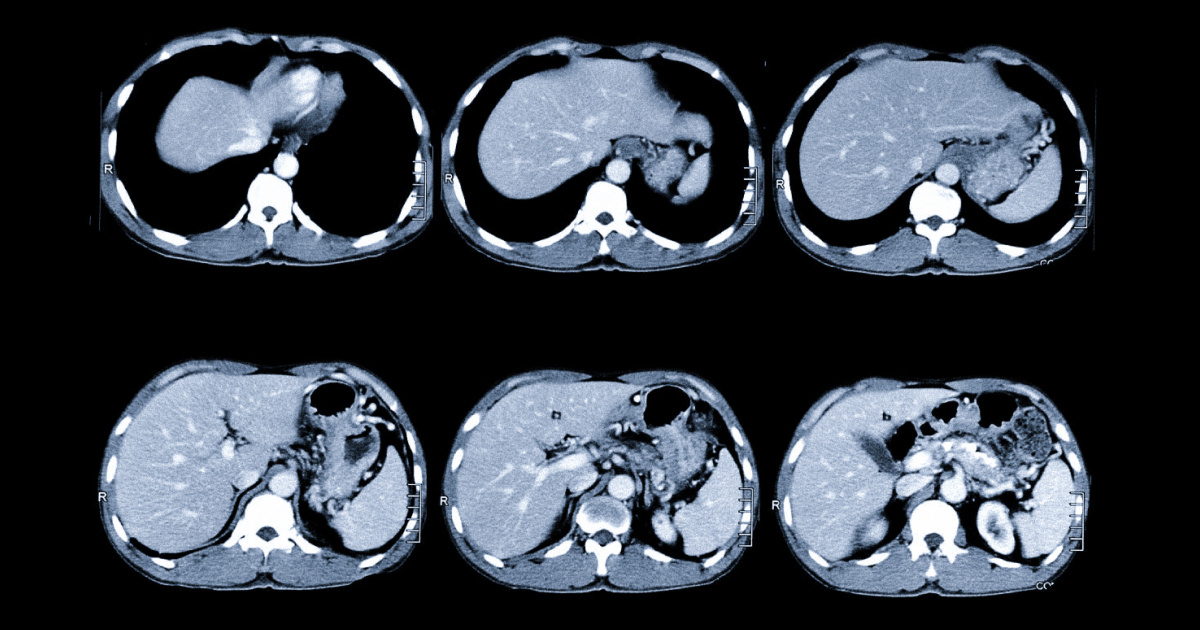

Комп’ютерна томографія (КТ) черевної порожнини є важливим діагностичним інструментом, що дозволяє лікарям детально оцінити стан внутрішніх органів, зокрема печінки та нирок. Основна мета КТ – виявлення патологічних змін у паренхіматозних органах, виявлення калькульозу (каменів), оцінка наявності вільної рідини, стану портальної вени та можливих ознак панкреонекрозу.

Паренхіматозні органи, такі як печінка та нирки, часто піддаються різним патологічним змінам, які можуть бути виявлені за допомогою КТ. У печінці лікарі шукають ознаки цирозу, пухлин, кіст або жирової дистрофії. У нирках КТ допомагає виявити пухлини, кісти, аномалії розвитку та інші патології.

Портальна вена, яка є ключовою судиною в системі кровообігу печінки, також підлягає оцінці під час КТ. Лікарі шукають ознаки тромбозу, аневризми або інших аномалій, які можуть вплинути на функціонування печінки.